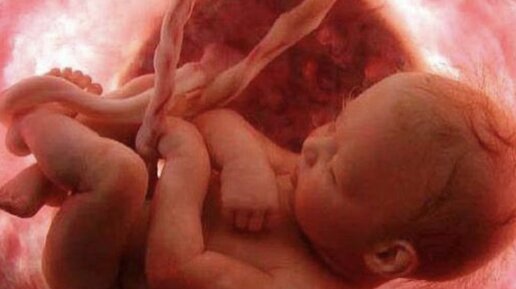

Одно из важных желаний будущей мамы: «Пусть малыш ляжет головкой вниз»..... Природа предусмотрела, чтобы ребёнок рождался головкой вперёд и в большинстве случаев именно так и происходит и за 4 недели до родов малыш принимаем правильное положение, чтобы естественные роды пошли легко, но, примерно, 6% малышей уже в животике у мамы начинают хулиганить и распологаются и ложатся так, как им хочется, например, ножками вниз. Многие мамочки очень переживают поэтому поводу и думаю, что при тазовом предлежание...

Иногда ребенок располагается к концу беременности в матке аномально, что может стать препятствием для самостоятельных родов. На протяжении беременности плод внутри полости матки много раз меняет свое положение, поворачиваясь то головкой, то ножками вниз. Относительно стабильное положение, которое сохранится уже до родов, он занимает примерно в 32-34 недели. Определенное положение малыша перед родами принято называть предлежанием. Особенности расположения крохи в матке и та часть, которая первой...